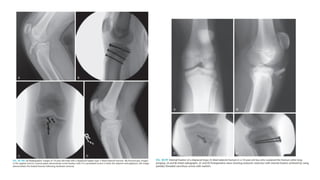

Treatment

• Nondisplaced fractures may

be treated in a long-leg cast.

• CT scan is essential to

determine the degree of

displacement.

• Articular displacement of >2

mm warrants operative

fixation, closed reduction and

percutaneous pinning or by

open reduction and internal

fixation.